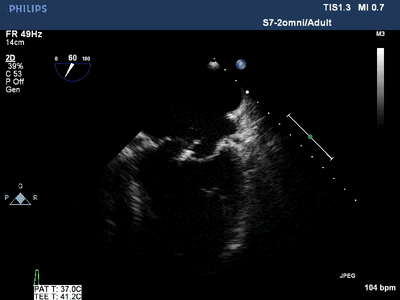

潍坊市第二人民医院技术导航心脏超声检查新视窗经食管超声心动图检查

心脏彩超图片

彩超心脏图片大全图片

心脏超声基本切面图解

正常心脏彩超

如何看懂心脏彩超图

正常心脏彩超图片

心脏彩超图片图解

心脏彩超图片图谱